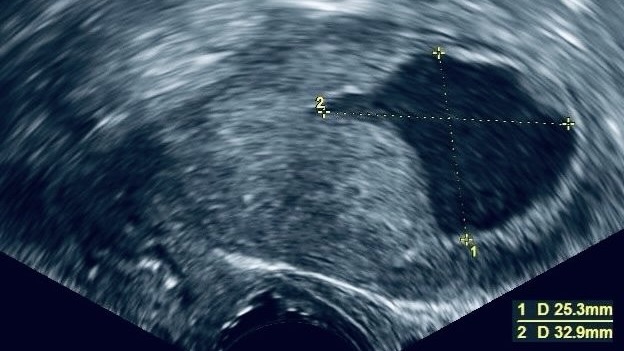

“The impact of endometrial fluid on single euploid frozen embryo transfers, to cancel or not?”

Title: The impact of endometrial fluid on single euploid frozen embryo transfers, to cancel or not?

Authors: Karishma Patel, Denny Sakkas, Brittany Morse, Daniel W Duvall Jr, Alan Penzias, Denis A Vaughan